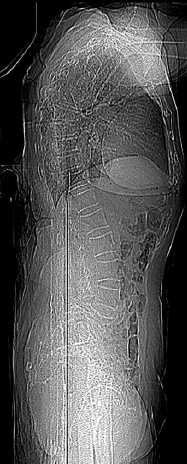

Paciente de 92 anos, sexo feminino, de forma abrupta e sem fator desencadeante, passou a sentir forte dor lombar que piorava à movimentação. A partir de então, deixou de caminhar devido à dor. Realizou uma radiografia de coluna lombar:

(Arquivo pessoal; imagem usada com autorização)

Diante desse achado, assinale a alternativa que apresenta o diagnóstico correto.